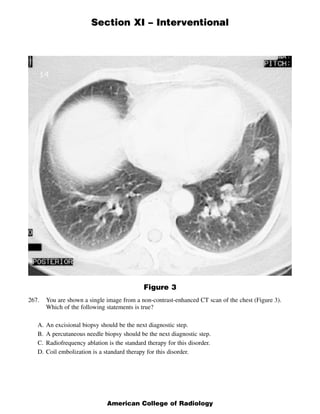

This document contains 5 clinical case scenarios involving interventional radiology procedures (questions 265-269). Each case is accompanied by an image and 4 possible answers. The correct answer is identified and a brief rationale is provided for each case. Question 270-279 continue testing knowledge of interventional radiology with additional multiple choice questions related to procedures, techniques, and disease processes.